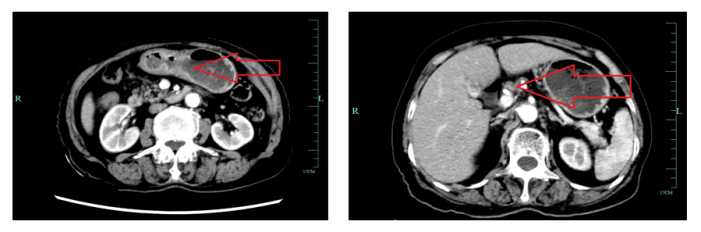

1)新辅助治疗2周期后,全腹CT平扫+增强(图3)示:胃窦部胃壁稍增厚,增强后黏膜不均匀强化,周围及小网膜见多发淋巴结显示,大者短径约8 mm,增强后见轻度强化。

图3 新辅助2周期后全腹CT平扫+增强